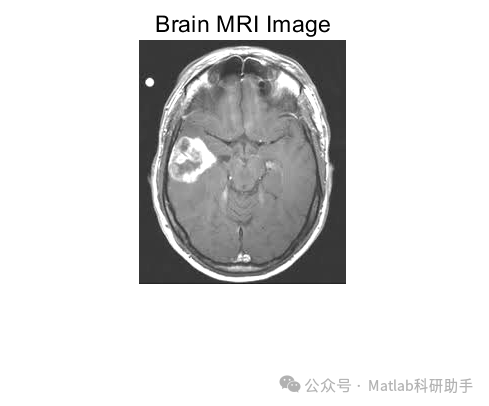

脑磁共振成像(MRI)作为一种非侵入性的医学影像技术,在神经科学研究和临床诊断中扮演着越来越重要的角色。通过对大脑结构和功能的详细描绘,MRI为理解大脑疾病提供了宝贵的信息。对大规模脑磁共振图像数据进行准确有效的分类,对于疾病的早期诊断、预后评估以及个性化治疗具有至关重要的意义。然而,脑磁共振图像数据通常具有高维度的特性,包含大量的冗余和噪声信息,这给传统的分类方法带来了挑战。为了克服这些问题,本文提出了一种基于主成分分析(PCA)和核支持向量机(Kernel SVM)的脑磁共振图像分类器。该分类器旨在利用PCA进行特征降维,提取图像中最具区分性的特征,然后利用Kernel SVM的高维非线性分类能力对降维后的特征进行分类,从而提高分类的准确性和鲁棒性。

脑磁共振图像分类是模式识别在医学影像领域的典型应用。其主要目标是将不同的脑磁共振图像样本划归到预定义的类别中,例如正常脑、阿尔茨海默病患者脑、轻度认知障碍患者脑等。然而,实现高精度和高效率的脑磁共振图像分类面临诸多挑战: